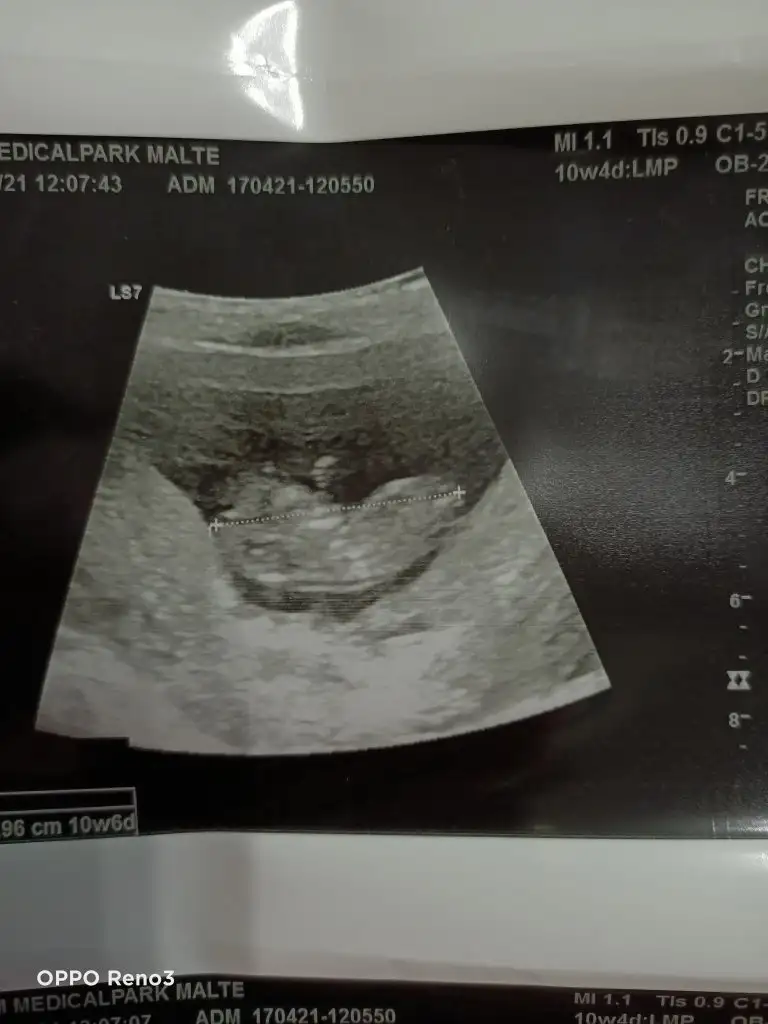

Tahminde bulunurmusun